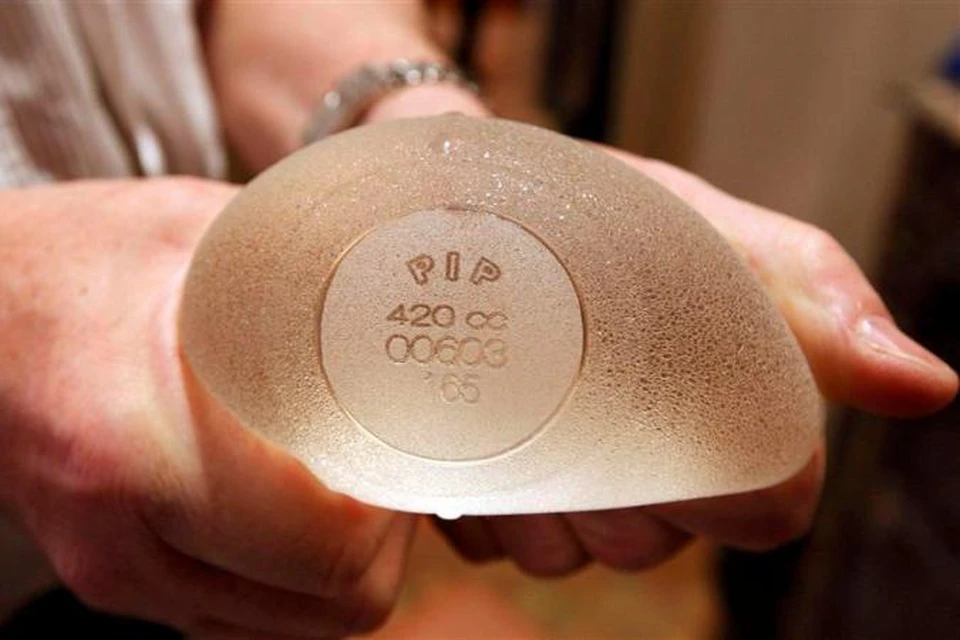

Анатомические импланты Eurosilicone

Раздел: Визуальный дайджест